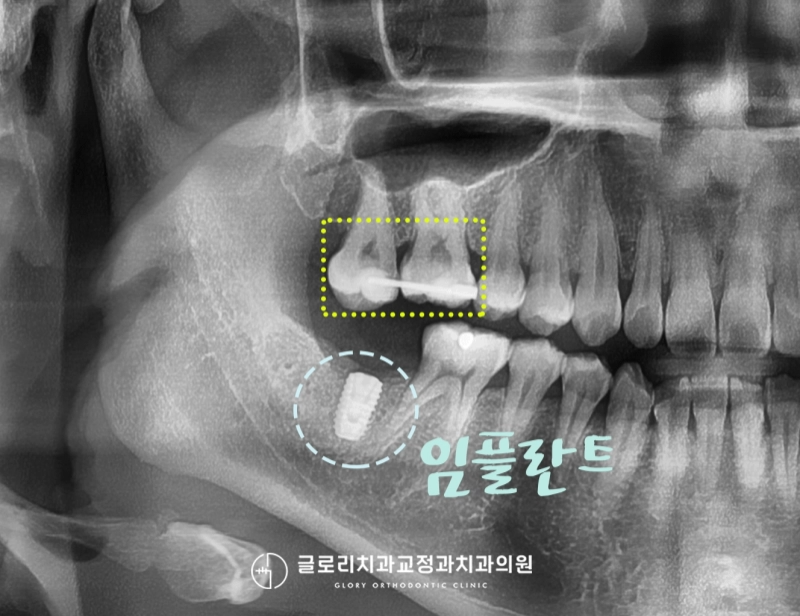

환자께서 말씀하신 내용을 토대로

먼저 엑스레이를 천천히 살펴보았습니다.

엑스레이에서도 보실 수 있듯이

오른쪽 아래 치조골 속으로

박혀 있는 임플란트의 인공치근을

관찰할 수 있었는데요.

그곳 바로 위 대합 되는 곳에는

어금니 두 개 무언가로 연결해둔 것 또한

확인할 수 있었습니다.